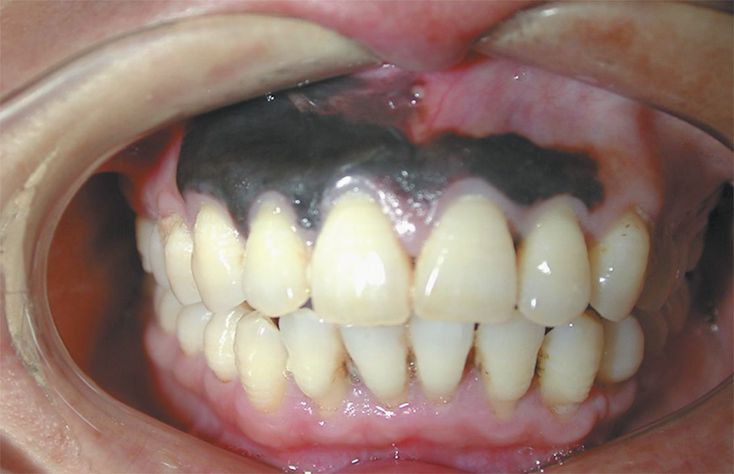

An otherwise healthy 45-year-old man presented with a 4-week history of nonpainful discoloration of the maxillary gingiva. He had no history of pigmented skin lesions. Intraoral examination showed areas of the gingiva that were black. The lesion was a pigmented macule, 1.5 cm by 4 cm in greatest dimension, with asymmetric and irregular borders and colors. Histopathological examination revealed an infiltrating lentiginous melanoma. Oral melanoma is a rare neoplasm. Exposure to the sun is clearly linked to cutaneous melanoma but is not clearly associated with oral melanoma. The patient underwent partial maxillectomy with 2-cm margins, but he declined adjuvant radiotherapy and chemotherapy. No pathologic lymph nodes were found. At follow-up 6 months after surgery, there were no signs of tumor recurrence.